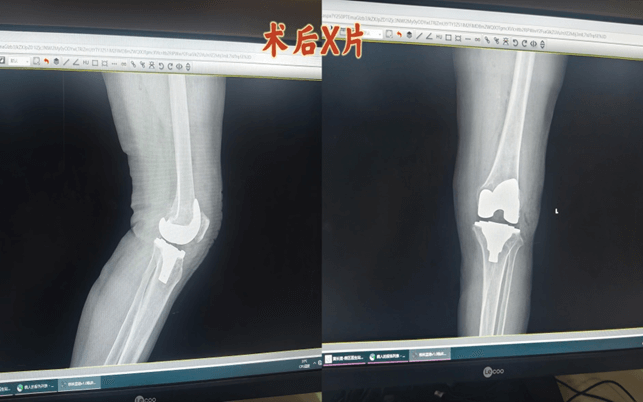

案例:患者女,69岁,系“反复左膝关节疼痛10余年,加重伴行走受限1月”入住我科。